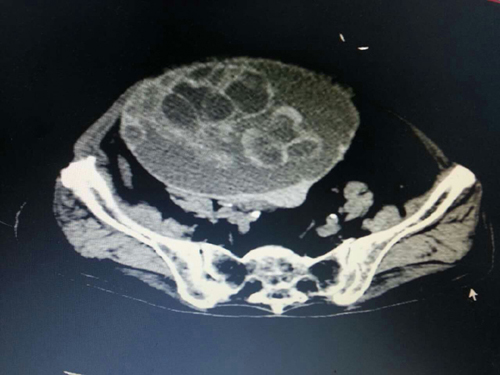

羅奶奶,衡南縣人,98歲高齡,平時跟兒子居住在桂林,2016年1月10日突發(fā)劇烈腹痛,在當(dāng)?shù)蒯t(yī)院就診,確診為“腹腔巨大腫瘤”,急需手術(shù)治療,但因羅奶奶年事已高,耐受手術(shù)能力差,手術(shù)風(fēng)險高,桂林多家大醫(yī)院均拒絕收治。羅奶奶兒子焦急萬分,通過家鄉(xiāng)親戚介紹,慕名前來我院肝膽外科?;颊呷朐汉蠼?jīng)急診CT檢查示:腹腔有一大小15.×16×18cm巨大腫瘤,腫瘤已經(jīng)扭轉(zhuǎn),開始破裂出血,病情十分危重,羅奶奶危在旦夕,只有急診手術(shù)才有一絲希望??粗颊咄纯嗟拿嫒荨⒓覍倨谂蔚哪抗?,手術(shù)做還是不做?如何去做?如果不做手術(shù),患者隨時有生命危險;如果做,年邁體弱的患者能否承受麻醉以及手術(shù)的打擊,能否安全度過圍手術(shù)期,疾病能否得到根治?“醫(yī)者仁心,我無法拒患者于門外,并且我相信我們的科室、我們的團隊、我們的醫(yī)院有這個能力完成這個高難度的手術(shù)!”肝膽外科主任李珍發(fā)如是說。經(jīng)過精心、細致、周密的圍手術(shù)期準(zhǔn)備后,李珍發(fā)主任、副主任醫(yī)師蔣水平帶領(lǐng)科室手術(shù)團隊,在麻醉科主任段雪琴的密切配合下,成功為患者摘除重達10余斤的腹部巨大腫瘤。術(shù)后,在許敏護士長帶領(lǐng)的護理團隊精心護理下,羅奶奶恢復(fù)順利,能下床自由活動,未出現(xiàn)任何并發(fā)癥,10日后痊愈出院。出院時,羅奶奶及全家感激不已,特向科室送來感謝信和錦旗。